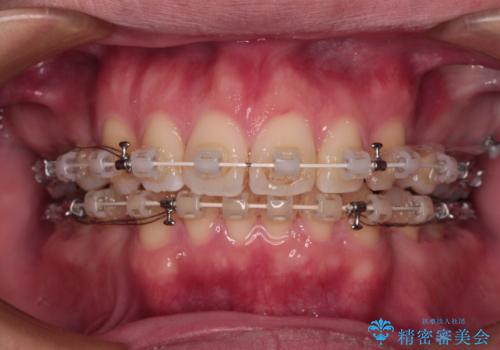

- 審美装置

- 2年1ヶ月

左上はアンカースクリューを併用することでスムーズに抜歯スペースを閉じることができました。